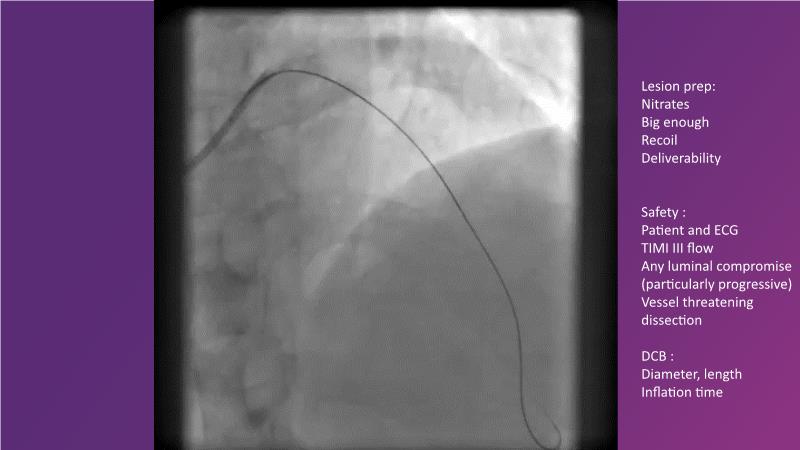

DES and DCB, can these two technologies be complementary for the treatment of the same patient? What are the advantages and how to proceed? You will know everything by watching this presentation based on concrete cases.